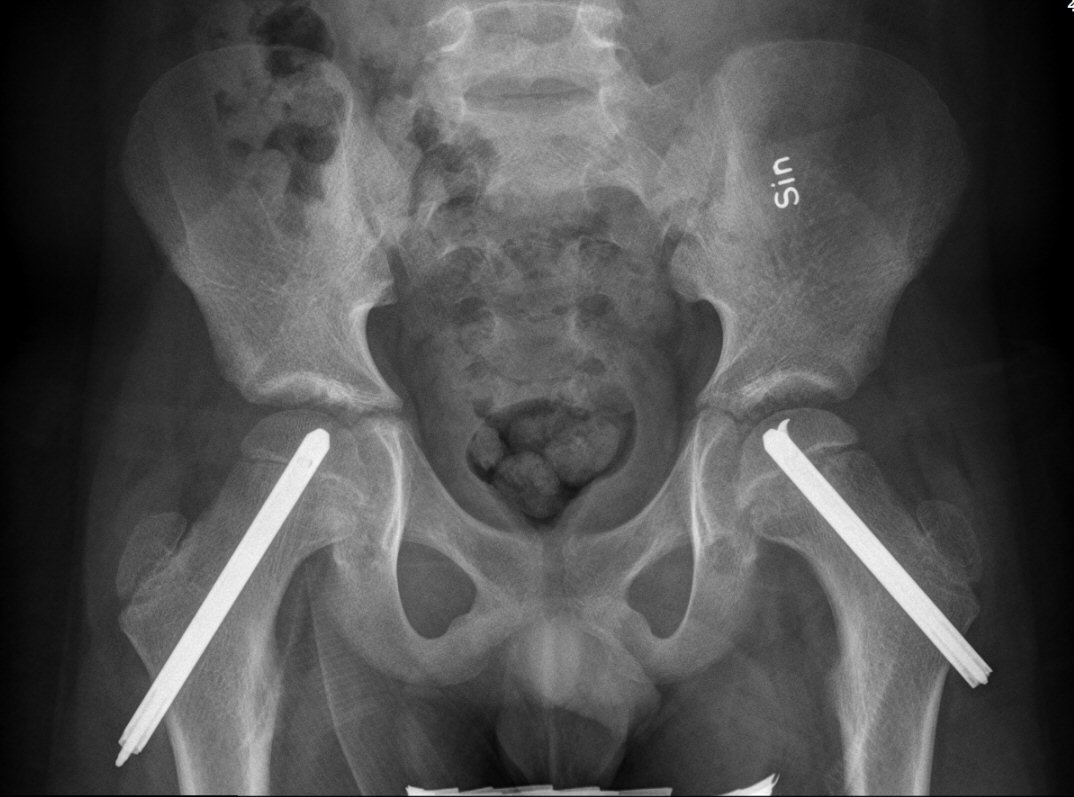

Fysiolys vänster höft akut, efter primär operation resp. innan spikextraktion efter 6 år

- T.ex. LIH-spikning med 1 eller 2 spik, incision betydligt mer anteriort än vanligt, spikarna riktas mer posteriort [3]

- Ofta profylaktisk spikning kontralateral sida pga. upp till 80 % risk för bilateral fyseolys [3]